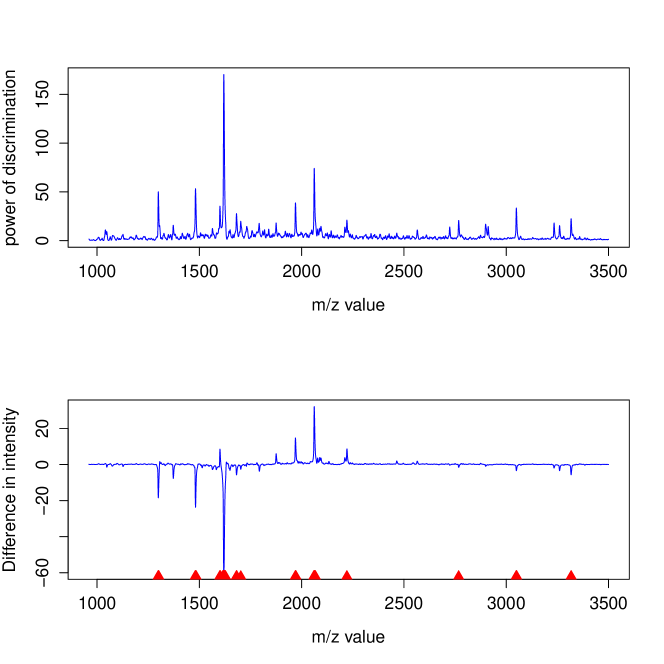

More importantly, Fisher-EM provides information which can be interpreted a posteriori to better understand both the data and the phenomenon. Indeed, the values of the estimated loading matrix , which is a matrix here, expressed the correlation between the discriminative subspace and the original variables. It is therefore possible to identify the original variables with the highest power of discrimination. It is important to highlight that Fisher-EM extracts this information from the data in a unsupervised framework. Figure 9 shows the correlation between each original variable and the discriminative subspace on an arbitrary scale. The peaks of this curve correspond to the original variables which have a high correlation with the discriminative axis estimated by Fisher-EM.

Figure 10 plots the difference between the mean spectra of the classes cancer and control (cancer - control) and indicates as well, using red triangles, the most discriminative original variables (m/z values). It is not surprising to see that original variables where the cancer and control spectra have a big difference are among the most discriminative. More surprisingly, Fisher-EM selects the original variables with m/z values equal to 2800 and 3050 as discriminative variables whereas the difference between cancer and control spectra is less for these variables than the difference on the variable with m/z value equal to 1350. Such information, which have extracted from the data in a unsupervised framework, may help the practitioner to understand the clustering results.